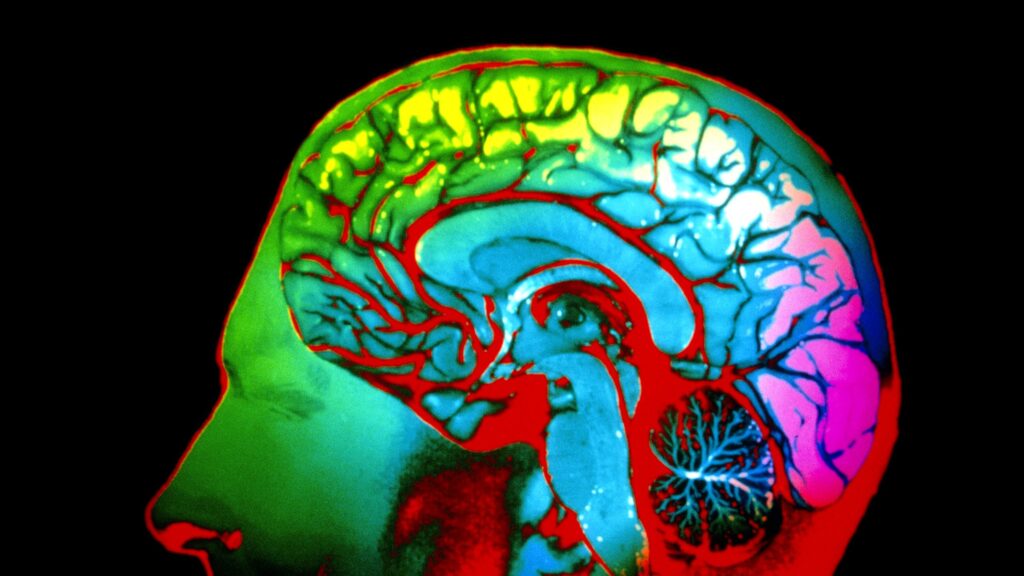

Color perception begins in the eye, where light enters through the cornea and is focused by the lens onto the retina. The retina contains photoreceptor cells known as rods and cones. While rods are responsible for vision in low light and do not perceive color, cones detect color and are divided into three types: L (long wavelengths), M (medium wavelengths), and S (short wavelengths). Each type is sensitive to different parts of the light spectrum, allowing us to perceive a wide spectrum of colors. Recent studies published in 2024 emphasize the role of these cones in how individuals experience color. It’s reported that approximately 90% of people can identify a basic range of colors but might differ in nuanced shades, primarily based on lighting conditions and surrounding colors. This highlights the importance of context in color perception.

Furthermore, researchers have found that the brain’s interpretation of color can change based on an individual’s prior experiences and cultural background. A study published in a leading psychology journal noted that people from cultures with a rich vocabulary for color were better at distinguishing between similar hues compared to those with a limited vocabulary. This suggests that language may enhance our color discrimination abilities, merging the realms of linguistics and visual perception. To further explore how our diet impacts our perception, consider checking out this article on the healthiest grains, since nutrition can influence various cognitive functions.